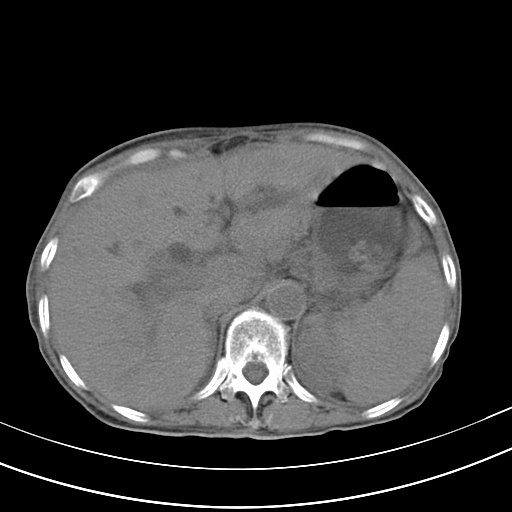

病人上腹部胀痛拌全身黄染八天

结石好象不明显吧?胆管稍扩张。

右侧少量胸水,胆囊增大,肝内胆管扩张,肝门部结构杂乱,建议增强。

肝内胆管及胰管扩张考虑为胰头区占位,肝门淋巴结增多,肝内多发低密度影,考虑为转移。门脉高压,脾大,胆囊大。

肝内胆管及胰管扩张,胰头增大考虑为胰头区占位,肝门淋巴结增多,考虑为转移。建议增强,脾大,胆囊大,壁厚,慢性胆囊炎。胃壁好像也增厚,且有一肿物。

1)考虑胰头癌并胆系低位梗阻;建议行ct增强扫描检查。2)慢性胆囊炎。3)脾大。4)少量腹水。5)双侧少量胸腔积液。